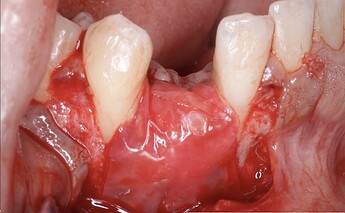

This case involved a missing #27, which was a previously failed implant site by another office. Another surgeon removed the implant and grafted the site (1). A flap was opened and revealed bone graft material that didn’t take. The entire site was cleaned out and we were left with the defect, as seen (2). An osteotomy was prepared and an implant was placed. We were optimistic about the success of the GBR, because there were nice bone peaks on adjacent teeth and the implant was well within the alveolar housing. GBR should be predictable in this case. (3,4).